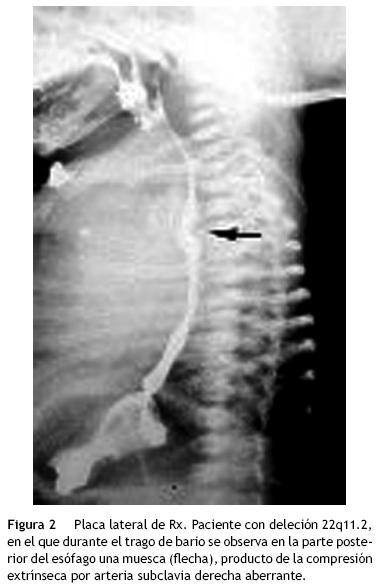

El estudio o abordaje de esta alteración en el periodo posnatal se inicia con la realización de un esofagograma con bario, en donde se observa la presencia de una muesca posterior de forma cóncava en la porción media del esófago (fig. 2).

El ecocardiograma bidimensional, en la proyección supraesternal en un corte longitudinal del arco, permite observar un arco aórtico izquierdo del que nacen 4 troncos supraaórticos (fig. 3).